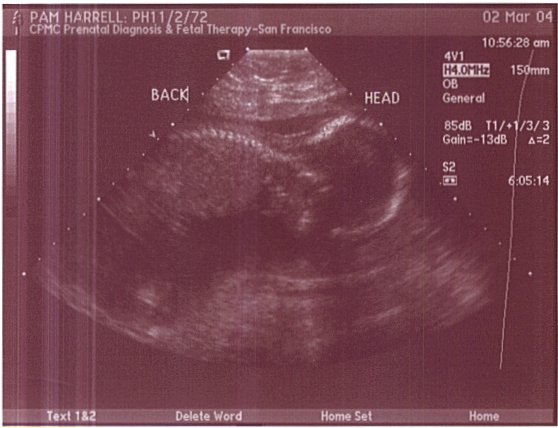

This is a profile shot of baby Harrell. Here you can see her spine clearly. This was taken on March 2, 2004.